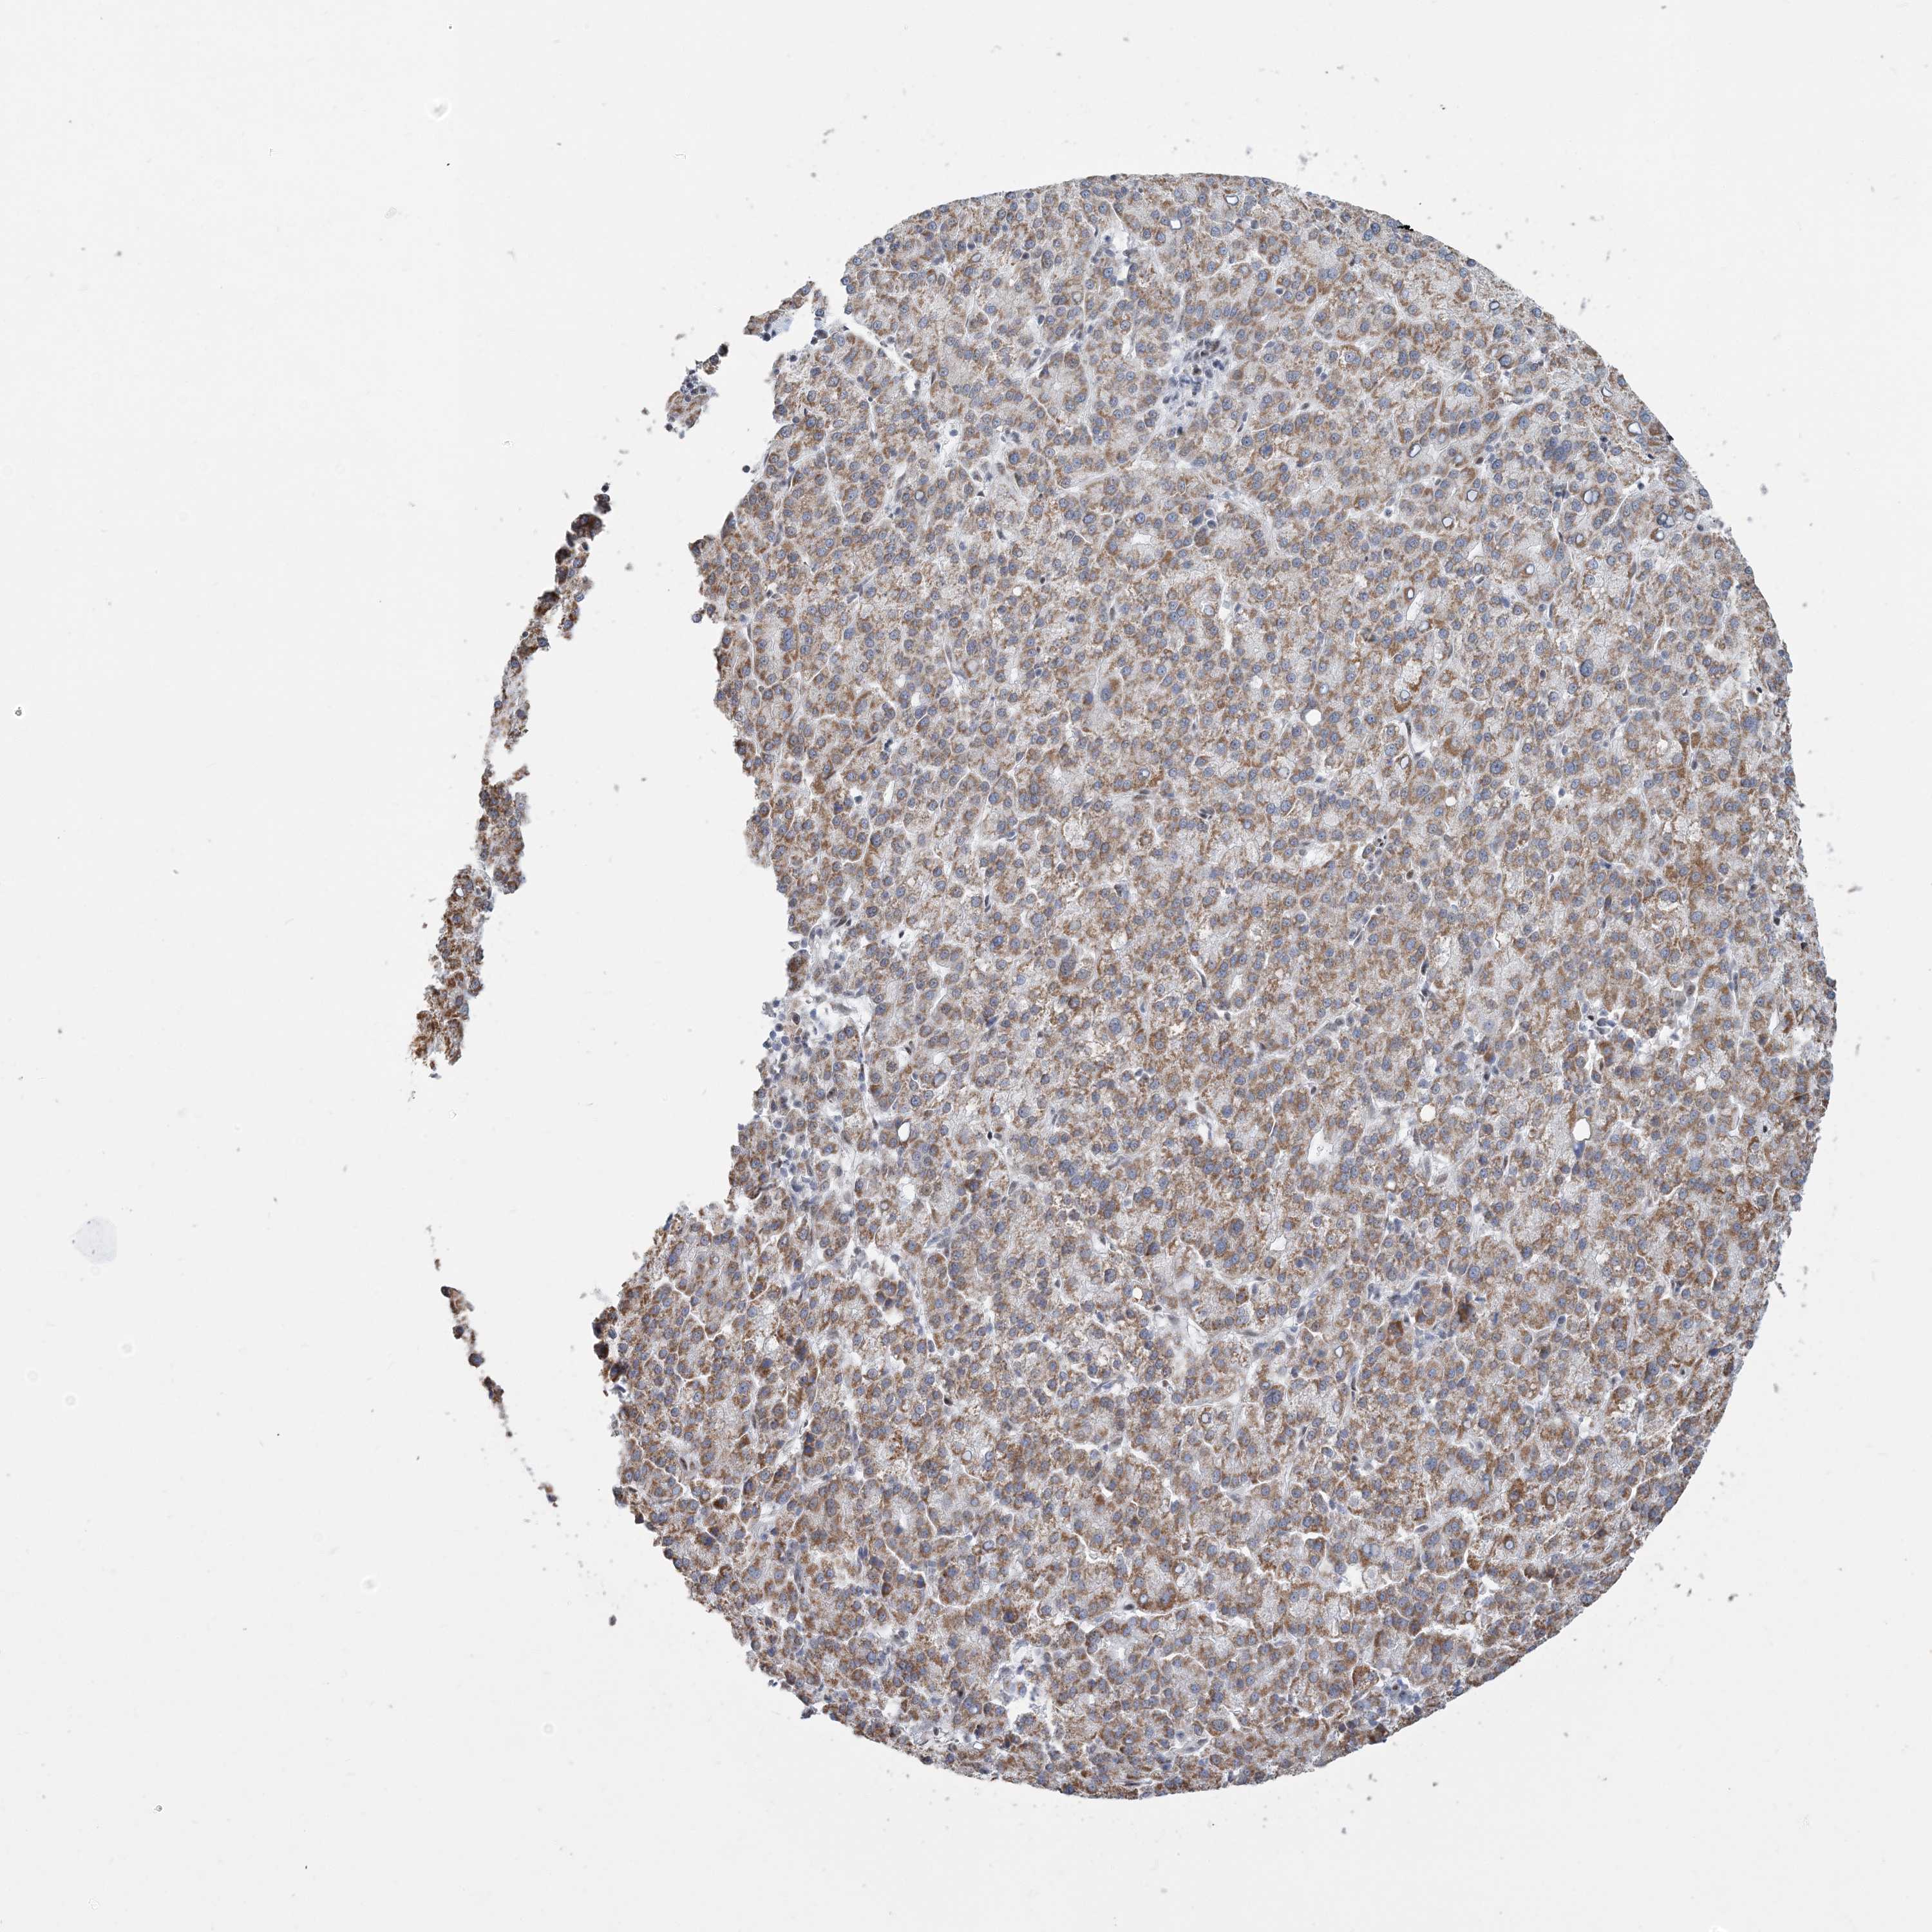

LIVER CANCER - Protein expressioni

A mouse-over function shows sample information and annotation data. Click on an image to view it in a full screen mode. Samples can be filtered based on level of antibody staining by selecting one or several of the following categories: high, medium, low and not detected. The assay and annotation is described here.

Note that samples used for immunohistochemistry by the Human Protein Atlas do not correspond to samples in the TCGA dataset.

Antibody stainingi

Antibody staining in the annotated cell types in the current human tissue is reported as not detected, low, medium, or high, based on conventional immunohistochemistry profiling in selected tissues. This score is based on the combination of the staining intensity and fraction of stained cells.

Each image is clickable and will lead to virtual microscopy that enables deeper exploration of all samples and also displays staining intensity scores, fraction scores and subcellular localization as well as patient and tissue information for each sample.

Antibody HPA036683

Antibody HPA036684

Staining

High

Medium

Low

Not detected

Intensity

Strong

Moderate

Weak

Negative

Quantity

>75%

75%-25%

<25%

None

Location

Nuclear

Cytoplasmic/membranous

Cytoplasmic/membranous,nuclear

Cholangiocarcinoma

Carcinoma, Hepatocellular, NOS